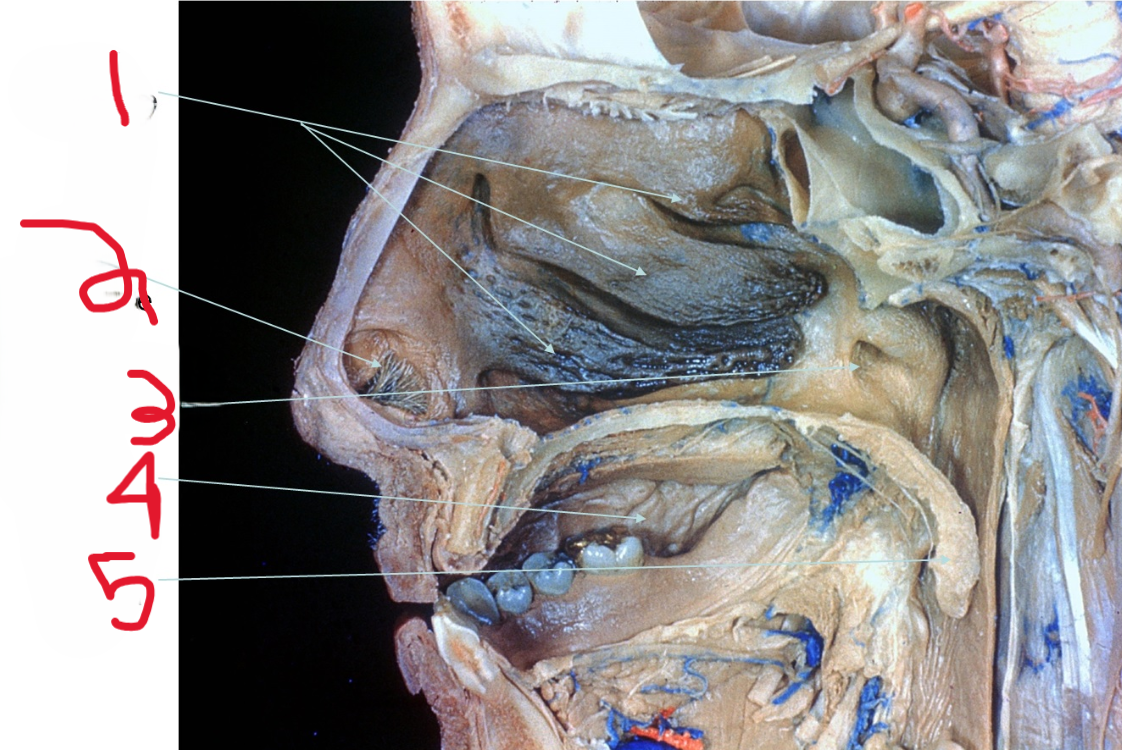

Nasal Conchae

What is depicted by #1

Nasal vestibule

What is depicted by #2

Opening of Pharyngotympanic (auditory) tube

What is depicted by #3

Oral cavity

What is depicted by #4

Uvala

What is depicted by #5